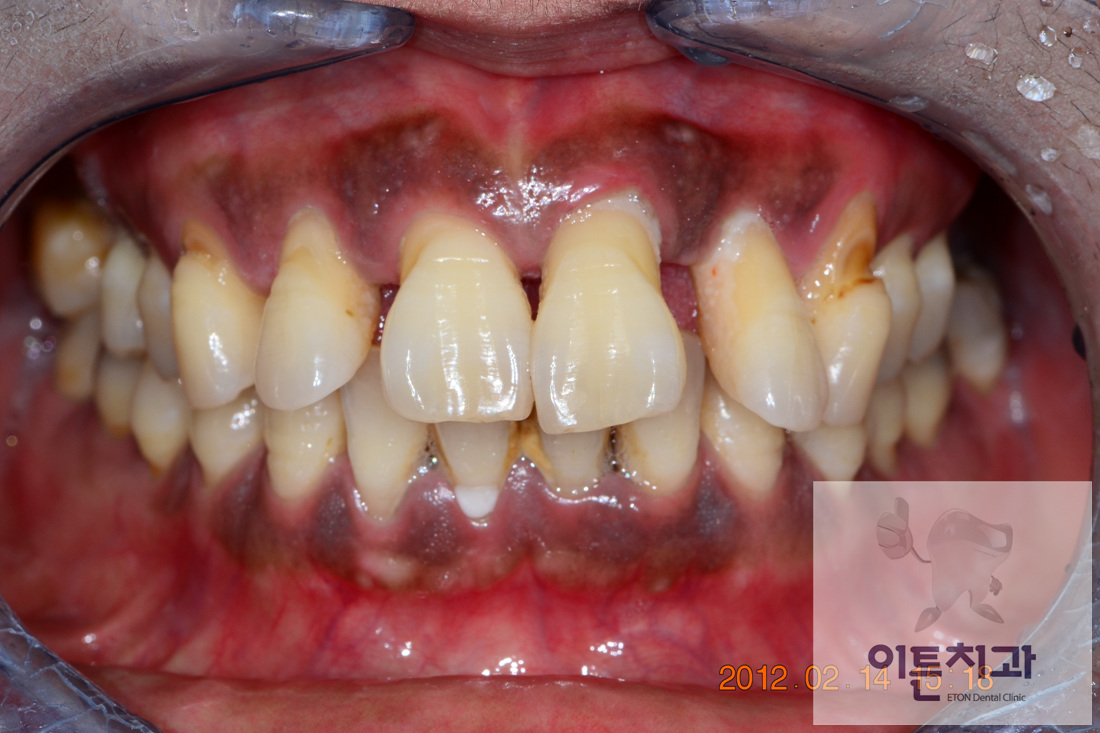

»ó¾Ç ÀüÄ¡ºÎ ºê¸´Áö ¹× ºÎºÐƲ´Ï Áõ·Ê

Before

½É°¢ÇÑ Ä¡ÁÖ ÁúȯÀ¸·Î ¿©·¯ Ä¡¾Æ¸¦ »ó½ÇÇϽŠ40´ë ¿©¼º ȯÀÚºÐÀ̽ʴϴÙ.

¾çÃø À§ ¾î±Ý´Ï ºÎÀ§´Â Ä¡ÁÖÁúȯÀ¸·Î »ÀÀÇ ¼Õ½ÇÀÌ ³Ê¹« ¸¹¾Æ ÀÓÇöõÆ®·Î ¼öº¹Çϱ⿡´Â ³Ê¹« ¸¹Àº Ä¡·á ºñ¿ë°ú ±â°£ÀÌ ÇÊ¿äÇßÀ¸¸ç, °á°úÀûÀ¸·Î »ç¿ëÇϱ⿡µµ Ʋ´Ï¸¸ ¸øÇÒ °ÍÀ̶ó´Â ÆÇ´ÜÀÌ µé¾ú½À´Ï´Ù.

±×·¡¼

1)ÁýÁßÀûÀÎ Ä¡ÁÖÄ¡·á¸¦ µ¿¹ÝÇϸé¼

2)¿¹ÈÄ ºÒ·®ÇÑ »ó¾Ç ¾çÃø ÃøÀýÄ¡(µÎ¹øÂ° ¾Õ´Ï)´Â ¹ßÄ¡ ÈÄ ºê¸´Áö·Î ¼öº¹ÇÏ¿´°í

3)¾çÃø À§ ¾î±Ý´Ï(¾çÃø »ó¾Ç ±¸Ä¡ºÎ)´Â ºÎºÐƲ´Ï·Î ¼öº¹ÇÏ¿´½À´Ï´Ù.

4)ÇÏ¾Ç ¾çÃø ´ë±¸Ä¡(Å« ¾î±Ý´Ï) ºÎÀ§ÀÇ ÃæÄ¡Ä¡·áµµ ½ÃÇàÇÏ¿´½À´Ï´Ù.

¿ìÃø »çÁøÀº Ä¡·á Á¾·á ÈÄ ¾à 1³âÀÌ °æ°úµÈ »óÅÂÀÌ¸ç ¾à°£ÀÇ Ä¡¼®ÀÌ Ä§ÂøµÈ °Í ¿Ü¿¡´Â

¸ðµç Ä¡¾Æ°¡ ¹®Á¦¾øÀÌ Àß À¯ÁöµÇ°í ÀÖ´Â »óÅÂÀÔ´Ï´Ù. ȯÀںв²¼µµ ¾Æ¹« ºÒÆí¾øÀÌ

¸Å¿ì ¸¸Á·½º·´°Ô »ç¿ë ÁßÀÎ ÄÉÀ̽ºÀÔ´Ï´Ù~